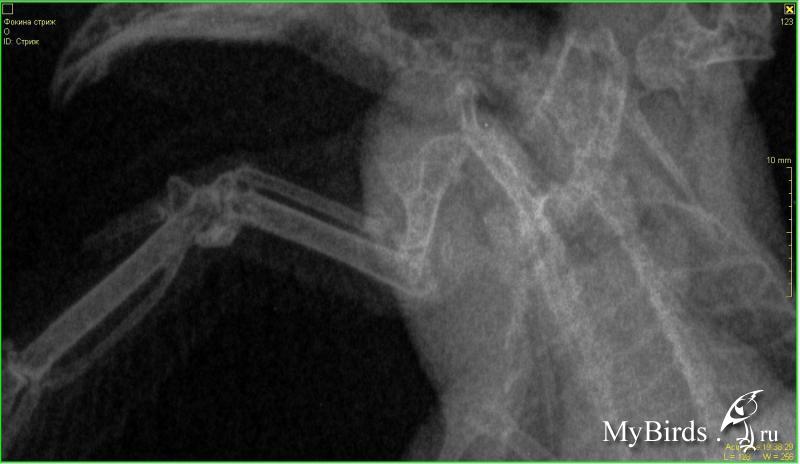

lilamor Опубликовано 27 июля, 2017 Автор #8 Опубликовано 27 июля, 2017 (изменено) кроме нашей страны и таких как мы с вами - стрижей на пмж никто не держит. нелетных сразу усыпляют.и не только потому, что дорого и трудоемко содержать, а потому что считают содежание птицы, абсолютно не приспособленной для земли издевательством над ней. нельзя сказать, что это полностью не соответствует истине. ни одна система стрижа на земле не функционирует так как надо, и создать для него сколько-либо оптимальные или комфортные условия невозможно. можно только относительно безопасные. поэтому, крайне редко бывает, что стрижи живут в домашних условиях больше года-двух. травмы, инфекции, перед которыми эти птицы беззащитны, отравления, тоска...большая коробка или вольер по типу выставочных клеток ладиоли для кошек (только сетка должна быть очень мелкоячеистая. перья так и так обобьет, но с большими ячейками может поломать крылья). идея - должно быть видно небо. очень желательна на зимний период времени уф-лампа. не использовать сено и солому.питание 3-4х разовое. до 12 грамм в сутки. потребности достаточно индивидуальны, но нельзя допускать истощения и ожерения. и то и другое смертельно опасно. очень обращать внимание на чистоту ног. осматривать состояние глаз, рта и дыхания. смотреть за изменением помета. любые наши болячки на пмж начинаются с этого. что-то забеспокоило - СРАЗУ обращаться, а не спустя недели и месяцы лечения от часто придуманных болячек, после чего птицу уже не спасти. еда - те же домовые и банановые сверчки, мраморные (очень желательно) и туркменские тараканы, перелинявший мучник. очень НЕ желательны такие жирные вещи как зофобас и огневка как личинкой так и мухой. лучше исключить полностью. пожизненно раз в неделю б1 (ампульный тиамина хлорид). на 40 грамм птицы 0,04 мл + 0,06 мл таурина (глазные капли тауфон). спаивать.из комплексных витаминов разве что нектон в период линьки.птице обязательно предлагать воду, избегать обезвоживания.возможно аккуратное купание из пульверизатора с теплой водой и аккуратной сушкой - не феном. тефлон смертельно опасен.о готовке на тефлоновой посуде так же придется забыть. Вот посмотрите, пожалуйста, это другой стриж, Фирка. Она жила у меня неделю, пока хозяйка была в отъезде. И скрины переписки с неизвестным мне рентгенологом. Сейчас стриж не раскрывает крыло в поврежденном суставе. Похоже на контрактуру. Видео прикрепить не получилось, но она держит это крыло прижатым к телу, в то время как здоровое крыло раскрывает полностью и хлопает. Оба крыла умеет поднимать вертикально вверх, потягиваться. Изменено 27 июля, 2017 пользователем lilamor

Anysya Опубликовано 27 июля, 2017 #9 Опубликовано 27 июля, 2017 да, если локтевой сустав разрушен, а это по всей видимости так, то это пмж без вариантов. не знаю зачем при закрытом переломе антибиотики, радует конечно, что с покрытием и зачем мелоксикам. ну, видимо, как противовоспалительное. но непонятно в таком случае как покой обеспечивать. а так все верно. к сожалению.